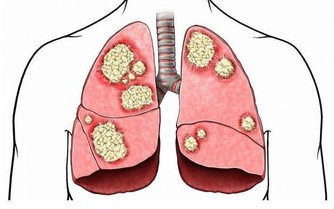

2.腹部青筋,俗話說;“青筋過肚”。這已經是比較嚴重的積滯;成人肝硬化腹水,腫瘤後期。腹部青筋往往是比較難治的疾病。